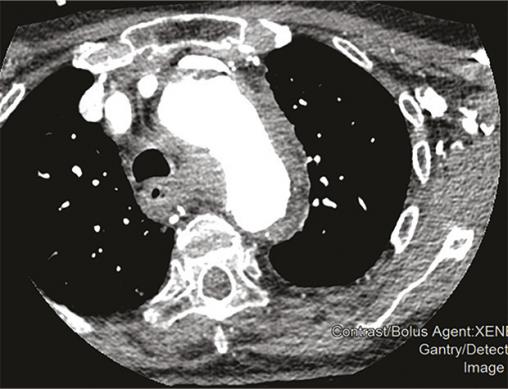

Cette femme de 95 ans arrivait aux urgences pour une douleur médiothoracique survenue brutalement quelques heures auparavant, transfixiante, sans irradiation ni facteur déclenchant évident. La patiente avait pour antécédents une hypertension artérielle (traitée par irbésartan et hydrochlorothiazide), une appendicectomie et une cholécystectomie. Devant une anisotension (différence de 30 mmHg de pression systolique [PAS] et 20 mmHg de diastolique entre les deux côtés), la patiente était placée en box de déchocage et monitoring continu. Un traitement par nicardipine au pousse-seringue électrique était instauré afin de contrôler cette hypertension majeure (221/114 mmHg), avec un objectif de PAS entre 150 et 170 mmHg. Le reste de l’examen clinique ne notait pas d’autres anomalies. Le bilan biologique montrait une élévation des D-dimères majeure (> 6 000 µg/L) et une insuffisance rénale. Malgré un débit de filtration glomérulaire (DFG) à 24 mL/min/m², la probabilité élevée d’une dissection aortique poussait à réaliser une tomodensitométrie thoraco-abdominopelvienne (fig. 1 et 2 ) avec injection de produit de contraste iodé, montrant un hématome intramural de la crosse de l’aorte. Après discussion pluridisciplinaire, l’indication chirurgicale était récusée du fait de l’âge avancé de la patiente et du risque opératoire.

Les syndromes aortiques aigus comprennent la dissection, l’ulcère et l’hématome intramural. Ce dernier, décrit pour la première fois en 1920,1 résulte d’une rupture des vasa vasorum sans déchirure intimale et est responsable de 10 à 40 % des syndromes aortiques aigus.2, 3 Le diagnostic se fait uniquement sur l’imagerie, généralement une tomodensitométrie thoracique injectée avec une augmentation d’épaisseur de la paroi aortique de plus de 5 mm.4 Néanmoins, il existe des facteurs clinico-biologiques d’orientation diagnostique comme l’asymétrie tensionnelle ou, selon certain auteurs, l’élévation des D-dimères.5 Selon sa localisation sur le trajet de l’aorte l’hématome est classé Stanford A ou B avec des taux de survie comparables aux dissections aortiques. Pouvant se résoudre de manière spontanée ou se rompre dans un tableau de dissection aortique, sa prise en charge fait débat. Ainsi, le traitement peut être médical avec contrôle tensionnel strict et surveillance monitorée des paramètres hémodynamique, ou chirurgical (mêmes indications que la dissection aortique). On peut également citer le traitement endo-aortique (pose d’une prothèse aortique synthétique par voie endoluminale) qui reste controversé en raison du risque d’endofuites secondaires, de pseudo-anévrismes ou de rupture intimale.6